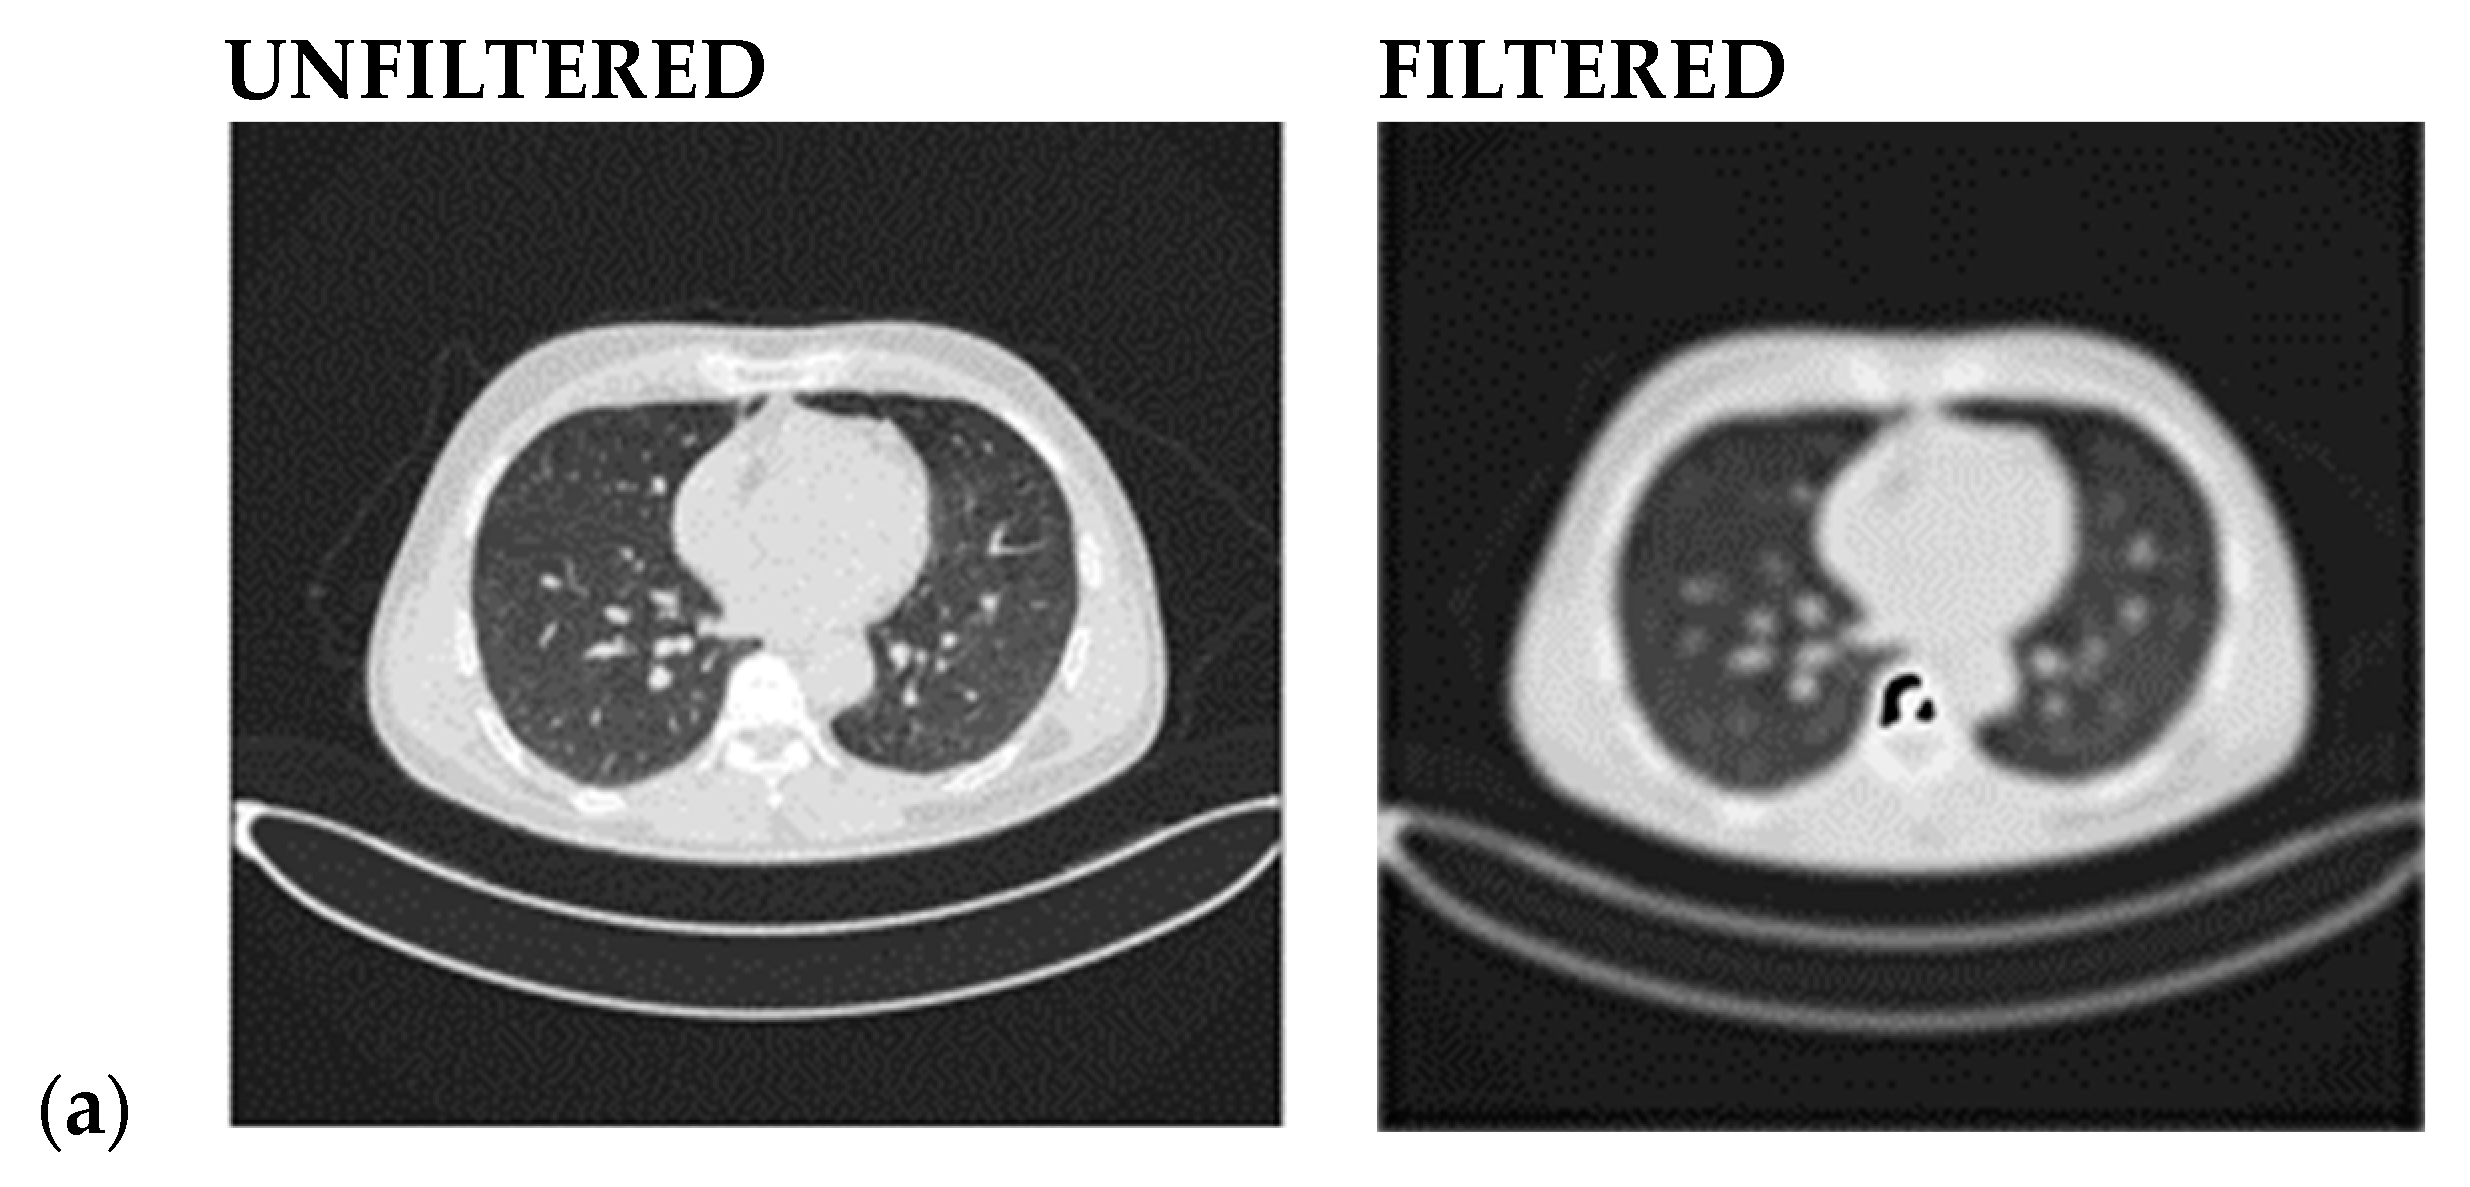

- A Butterworth smooth filter-based pre-processing can be applied to reduce the noise, that could be misinterpreted as features, before utilizing the CNN-based module. The efficacy of CNN models applied to smoothed images is investigated; this methodology provides good results in comparison to literature in which many attempts to segment lesions or increase the lesion quality, but this coincides with keeping noise that impacts the CNN models’ performance (i.e., accuracy) [21,22,23];

2.2.1. Smooth Filter-Based Pre-Processing